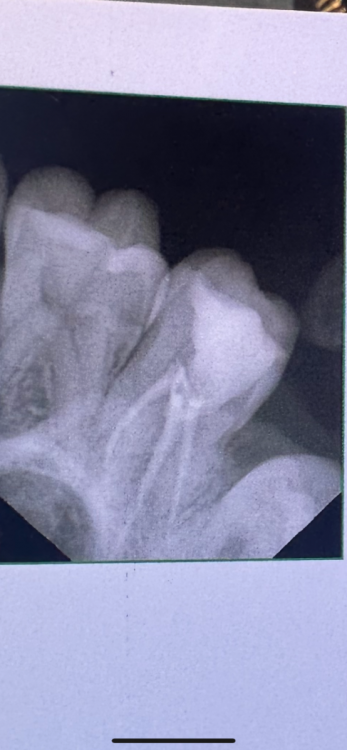

Здравствуйте!16 дней назад пролечили 7 верхний зуб. Сразу после началась сильная боль, которая держалась 2 дня и потом пошла на спад. На 7 день она остановилась и держится на одном месте. Зуб реагирует когда постучишь по временной пломбе. Когда поешь, потом начинал ныть. Так же легкие, редкие распирающие и пульсирующие боли. На зуб Накусывать неприятно. Несколько раз ломило от него все зубы, а до него было больно даже языком дотронуться.  В легком дискомфорте все это сохранялось 7 дней. На 13 день доктор распломбировала каналы, зуб поболел после распломбировки день, после вмешательства, как все утихло  и опять  я чувствую тот же дискомфорт, т е после распломбировки каналов ничего не изменилось, все держится на одном месте. сейчас в каналах кальций.Возможно ли что каналы зря распломьировали?  И проблема не в них. При удалении нерва доктор сказал, что кровь из канала не останавливалась, но потом промыла вроде остановилась и она его запломбировала.

Здравствуйте, скорее всего дело в четвертом канале, который пропустили(не нашли) и не обработали.  Сделайте КТ,  там видно будет,  что с четвертым каналом.